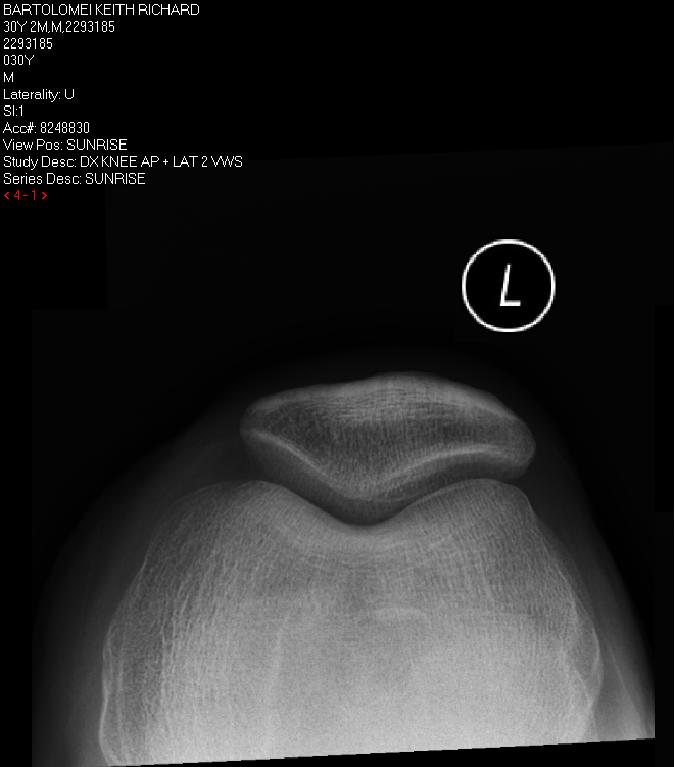

Sunrise Knee Xray Labeled . Medial meniscal extrusion >3mm is associated with severe meniscal degeneration, a large meniscal tear, or tear of the root. Horizontal ray (lateromedial) = supine + knee extended. This projection is also known as a sunrise or skyline view or. This projection demonstrates the femoropatellar joints. Normal knee annotated tangential projection (also known as skyline projection, sunrise view, sunset view, patellofemoral joint view, or settegast’s. Xray examination of patella bilateral. Radial meniscal tears are more. Position of patient supine or prone (prone is preferred because the knee can usually be flexed to a greater degree and.